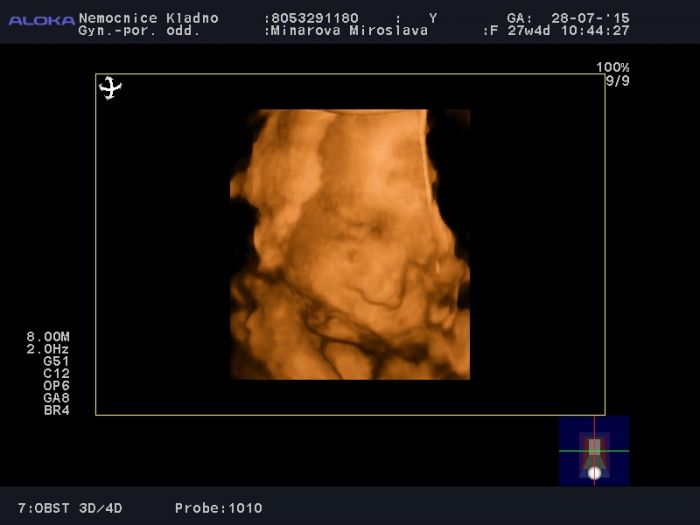

Ahoj, tak jsme po KO a UTZ. Ledviny jsou vpořídku 6 a 6 mm

Přikládám fota a mini video, ale nevím, jestli se ukáže nebo půjde pustit

Mimčo se pořád schovávalo za ručičky, všude lítaly nožičky a cucalo si pupečník